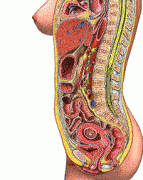

怀孕后肚子一天一天大起来,宝宝是健康成长了,那么准妈妈的内脏去哪儿了?本来就已经满满当当的身体多了一个宝宝,真好奇内脏们会不会害怕这个大怪兽侵占了房子,就好像房地...

从受精到一个婴儿的诞生,很多人都会觉得孕育一个生命是一个很神奇的过程,也很好奇胎儿是怎么在母体里生长变化的,今天小编就带大家看看从受孕到分娩,胎儿发育的整个过程。...